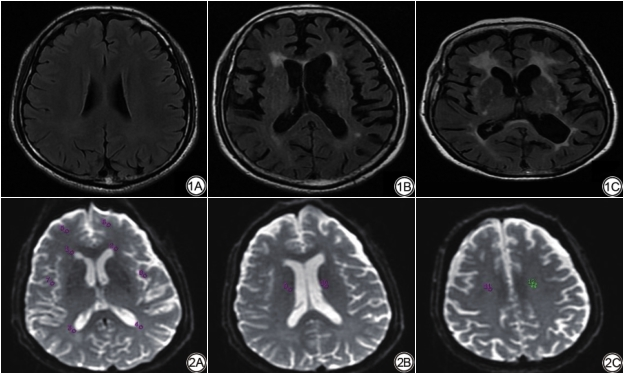

分析流程如下:首先对常规MRI图像(主要根据T2WI和FLAIR图像)采用Fazekas量表[14]进行WMHs视觉评分,根据评分标准分为A组(0分)30例、B组(1~3分)50例与C组(4~6分)30例(图1)。然后,依据T2WI和FLAIR图像选择感兴趣区(region of interest, ROI),测量选择区域包括:双侧额叶及颞叶皮层下、侧脑室前后角、放射冠区、半卵圆中心等部位的NAWM,ROI大小约20~40 mm2(图2),测量时将ASL与DTI图像进行融合,从而确保ROI在CBF图、各向异性分数(fractional anisotropy, FA)图和表观扩散系数(apparent diffusion coefficient, ADC)图的相同位置。

评价指标:(1)CBF反映大脑葡萄糖利用、耗氧、有氧糖酵解等功能代谢情况[15];(2)FA反映神经纤维的直径、密度、排列的一致性和髓鞘的完整性;(3)ADC反映水分子的扩散速度与范围(图3)。